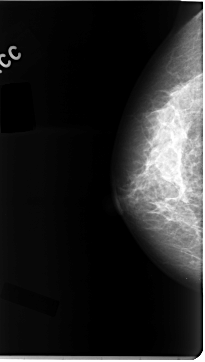

C_0113_1.RIGHT_CC

RIGHT_CC LINES 4704 PIXELS_PER_LINE 2656 BITS_PER_PIXEL 12 RESOLUTION 50 NON_OVERLAY